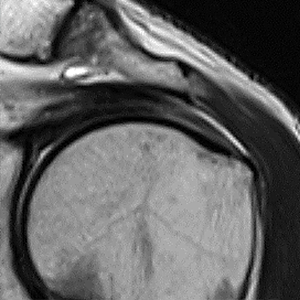

症例 3